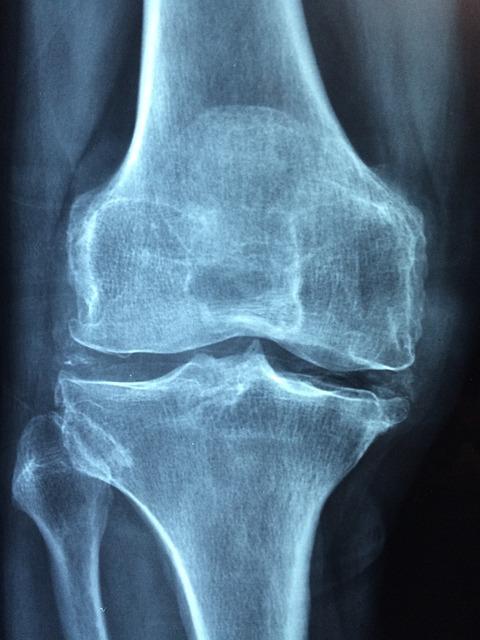

Imagine your joints like well-oiled hinges on a door. Cartilage acts as the smooth surface that allows the bones to glide over each other without friction. In OA, this cartilage wears down, causing the bones to rub together. This can lead to:

While OA can affect any joint, it most commonly occurs in the:

Knees: A leading cause of knee pain and disability